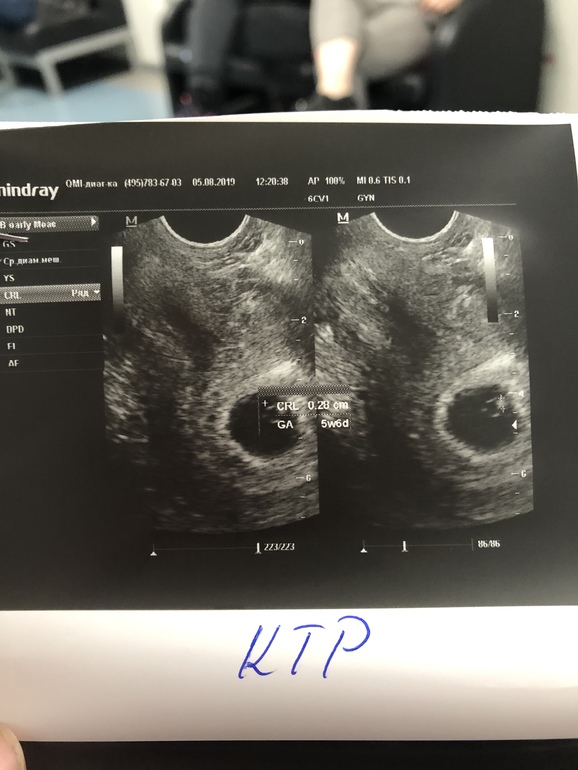

Я правильно поняла , что по этому методу у меня девочка ?😄 оооой хотелось бы очень))) спрошу сотый раз...у кого совпало?)

У меня с 4 дочками совпало, а остальные 2 нет узи на этом сроке просто. У вас, если узи вагинальное было, то доча в животике😊

Снимок в 7 недель. УЗИ вагинально делали. У меня в итоге мальчик.

более белое пятно

Видимо, да. Если всё правильно поняла. Жду мальчика.